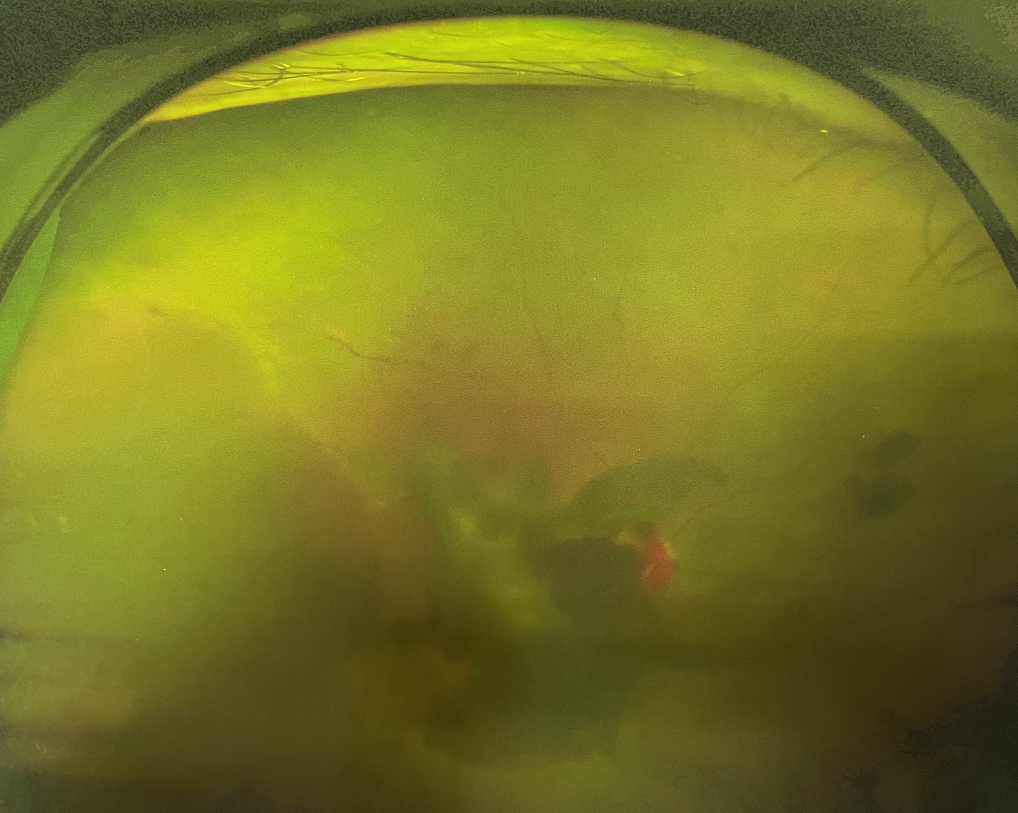

眼底出血是指眼內(nèi)視網(wǎng)膜出血,或玻璃體內(nèi)出血。眼底位于眼睛深處,所以這類出血只靠肉眼是看不到的,早期可能不紅、不痛、不癢,需通過專業(yè)的眼底檢查才可看到,往往短期內(nèi)就可造成視力驟降甚至失明!

同樣的,眼底出血也是一種癥狀,而非病種。誘發(fā)眼底出血的原因很多,常見的有全身性血管病和血液病、視網(wǎng)膜血管異常、機械性阻塞、炎癥性疾病或免疫復(fù)合物侵犯血管壁等。